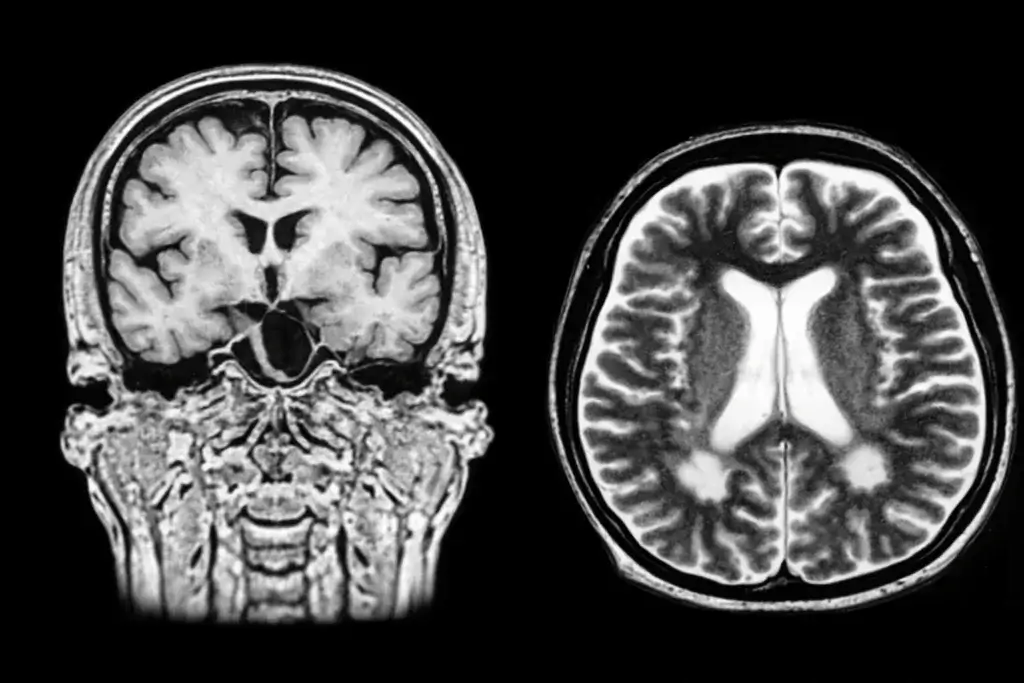

Uma nova análise de dados do estudo clínico de fase III TEMSO sugere que o tratamento com Aubagio (teriflunomida) pode desacelerar de forma significativa a atrofia cerebral em pessoas com esclerose múltipla remitente recorrente (EMRR). A perda de volume cerebral é considerada um marcador importante da progressão da doença e está associada ao declínio neurológico […]